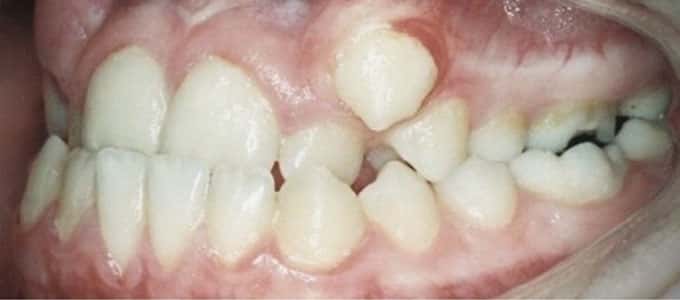

Tratamentul ortodontic este un proces biologic complex care include modificări ale oaselor maxilare, faciale și ale țesuturilor moi pe măsură ce dinții sunt mișcați în noile poziții.

Tratamentul ortodontic nu este o soluție rapidă. Acesta începe întotdeauna cu o examinare minuțioasă a dinților, a buzelor și a întregului aspect facial, sunt necesare radiografii si fotografii de diagnostic. Din aceste informații detaliate medicul ortodont dezvoltă un plan de tratament personalizat.